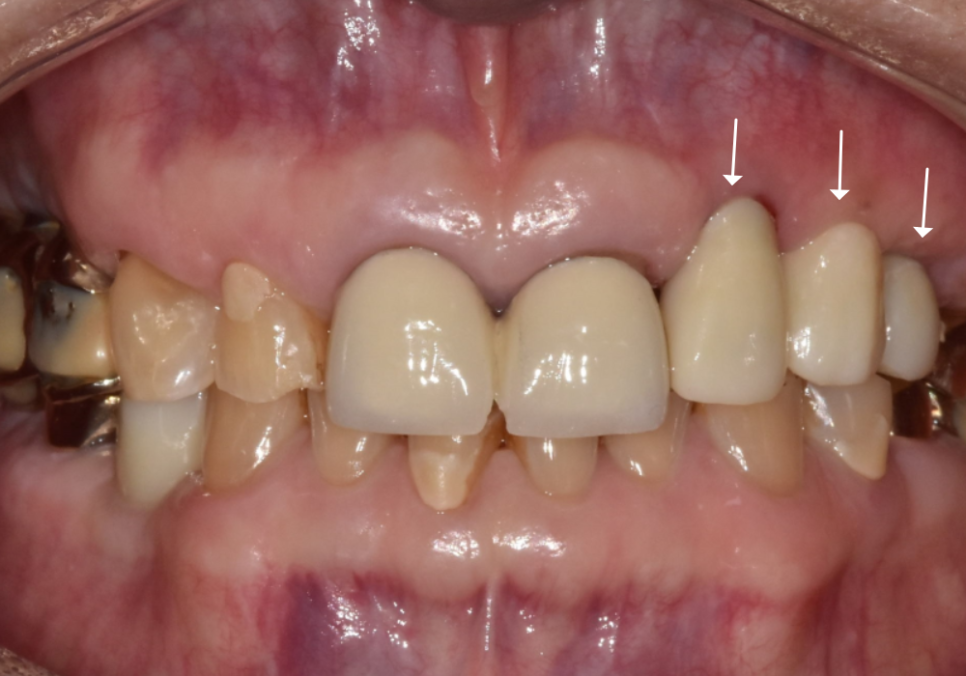

그 후 4개월이 지나, 임플란트 뿌리와 뼈가

단단하게 굳은 것을 확인한 뒤,

지르코니아로 보철물을 올려드려

치료를 마무리했습니다.